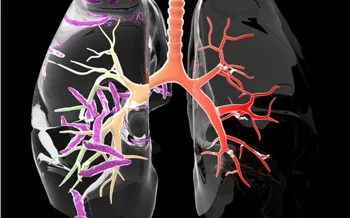

• Study Explains Increased Risk of TB for Smokers

'Clogged-up' immune cells are to blame.

• A ‘Game-Changer’ – Latest TB Research From Trinity

New findings especially useful for drug-resistant forms of the disease